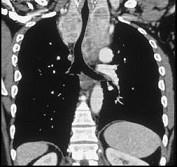

问题 男,33岁,颈部包块半年余,可随吞咽上下移动,请结合影像学检查,选出最可能的诊断 ( )

选项 A.胸腺瘤 B.淋巴瘤 C.纵隔畸胎瘤 D.淋巴管瘤 E.胸骨后甲状腺肿

答案 E